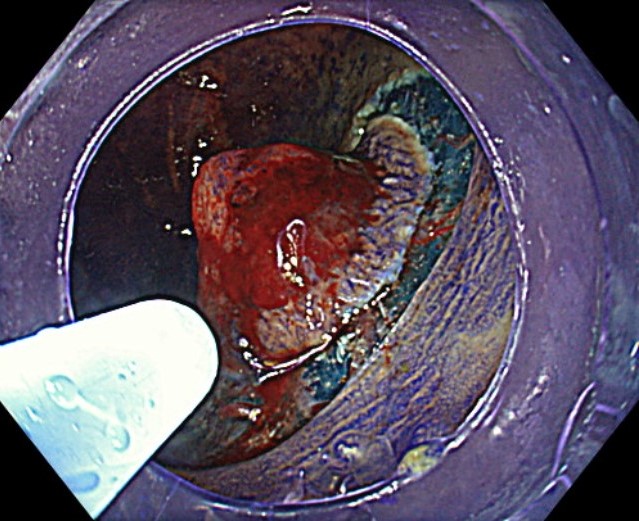

1. WL

WL observation shows a protruding, reddened lesion. At first glance, the surface appears smooth. Chicken skin spots are seen around the lesion.

Red dilated blood vessels are observed on the surface.